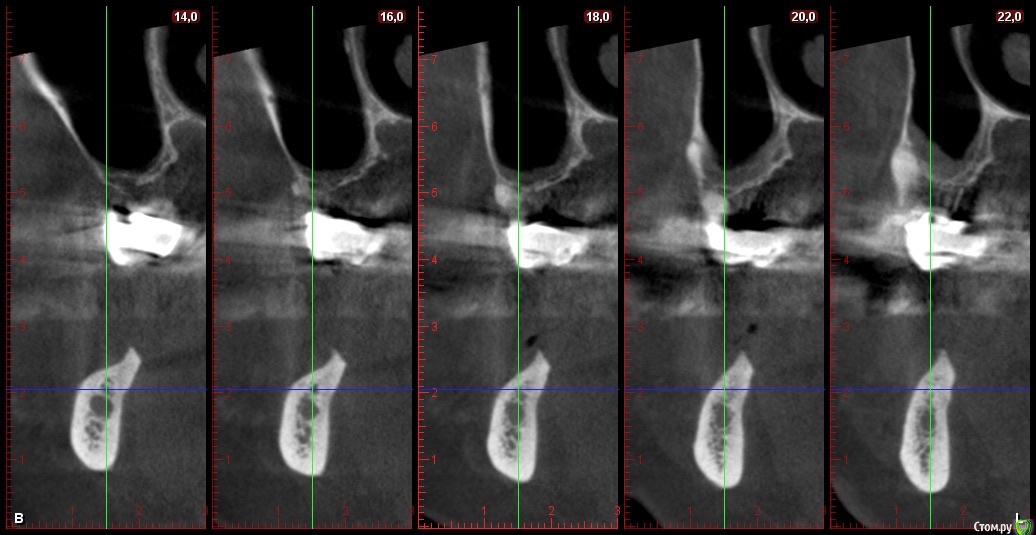

Глеб Митрофанов Опубликовано 22 октября, 2015 Автор Поделиться Опубликовано 22 октября, 2015 Срезы кт Ссылка на комментарий

Глеб Митрофанов Опубликовано 23 октября, 2015 Автор Поделиться Опубликовано 23 октября, 2015 (изменено) Спасибо за кейс.Скажите пожалуйста какая высота кости до нижнечелюстного канала?Спасибо.До канала , в самой низшей точке - 4,5-5 мм Изменено 23 октября, 2015 пользователем Глеб Митрофанов Ссылка на комментарий